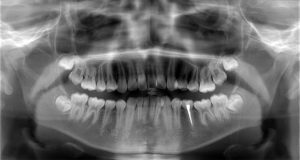

たとえばこちら

歯の中心に突起があるのがわかるでしょうか?

よく見てみると、ツノのようなものが生えているような状態があります。

上で上げている写真のお子さんも、実は中心結節が折れていましたが、レントゲン写真より神経は中になく症状もなかったので一安心でした。